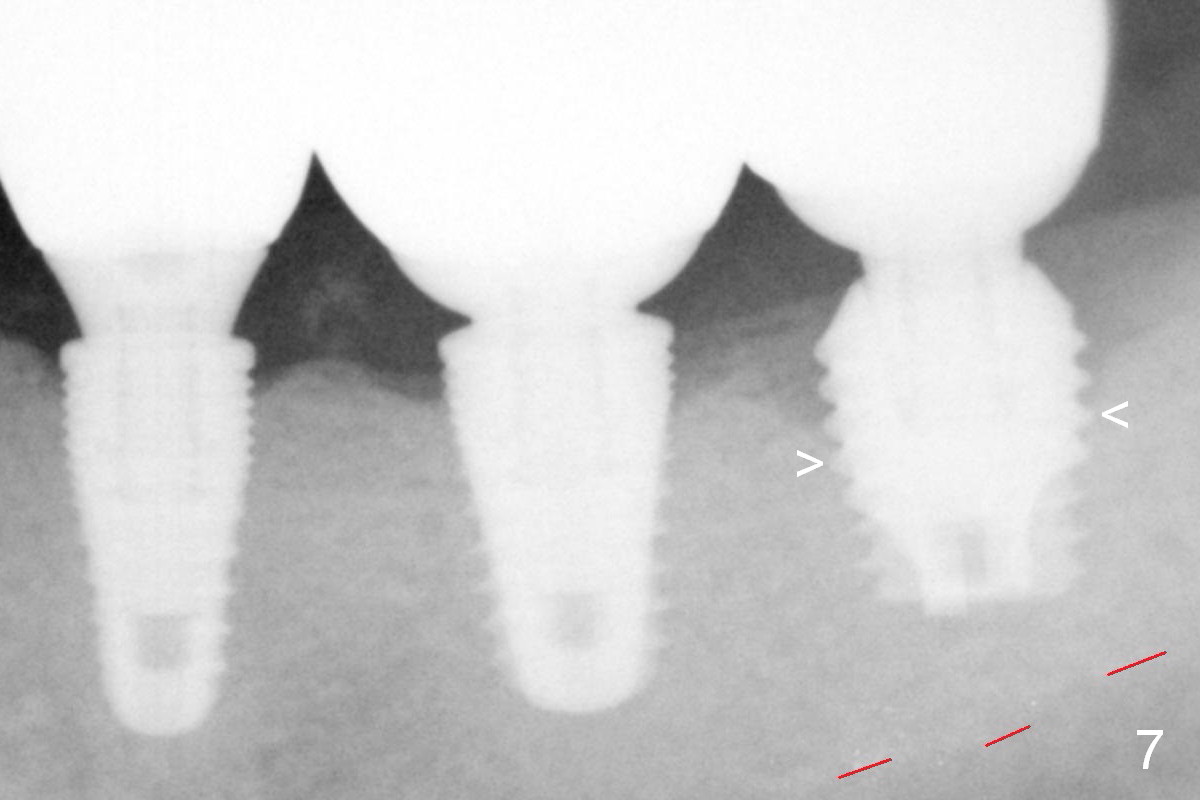

Five months post cementation, the patient returns because of loose abutment screw at #18. Bone resorption is noted (Fig.7 arrowheads). His oral hygiene is fair. He refuses implant at #2, saying that he dares not to chew on the left. When the screw became loose again 3 months later, he accepted the treatment. The implant at #19 is loose with a gap between the implant and the bone 3 years 5 months post cementation (Fig.12 *).